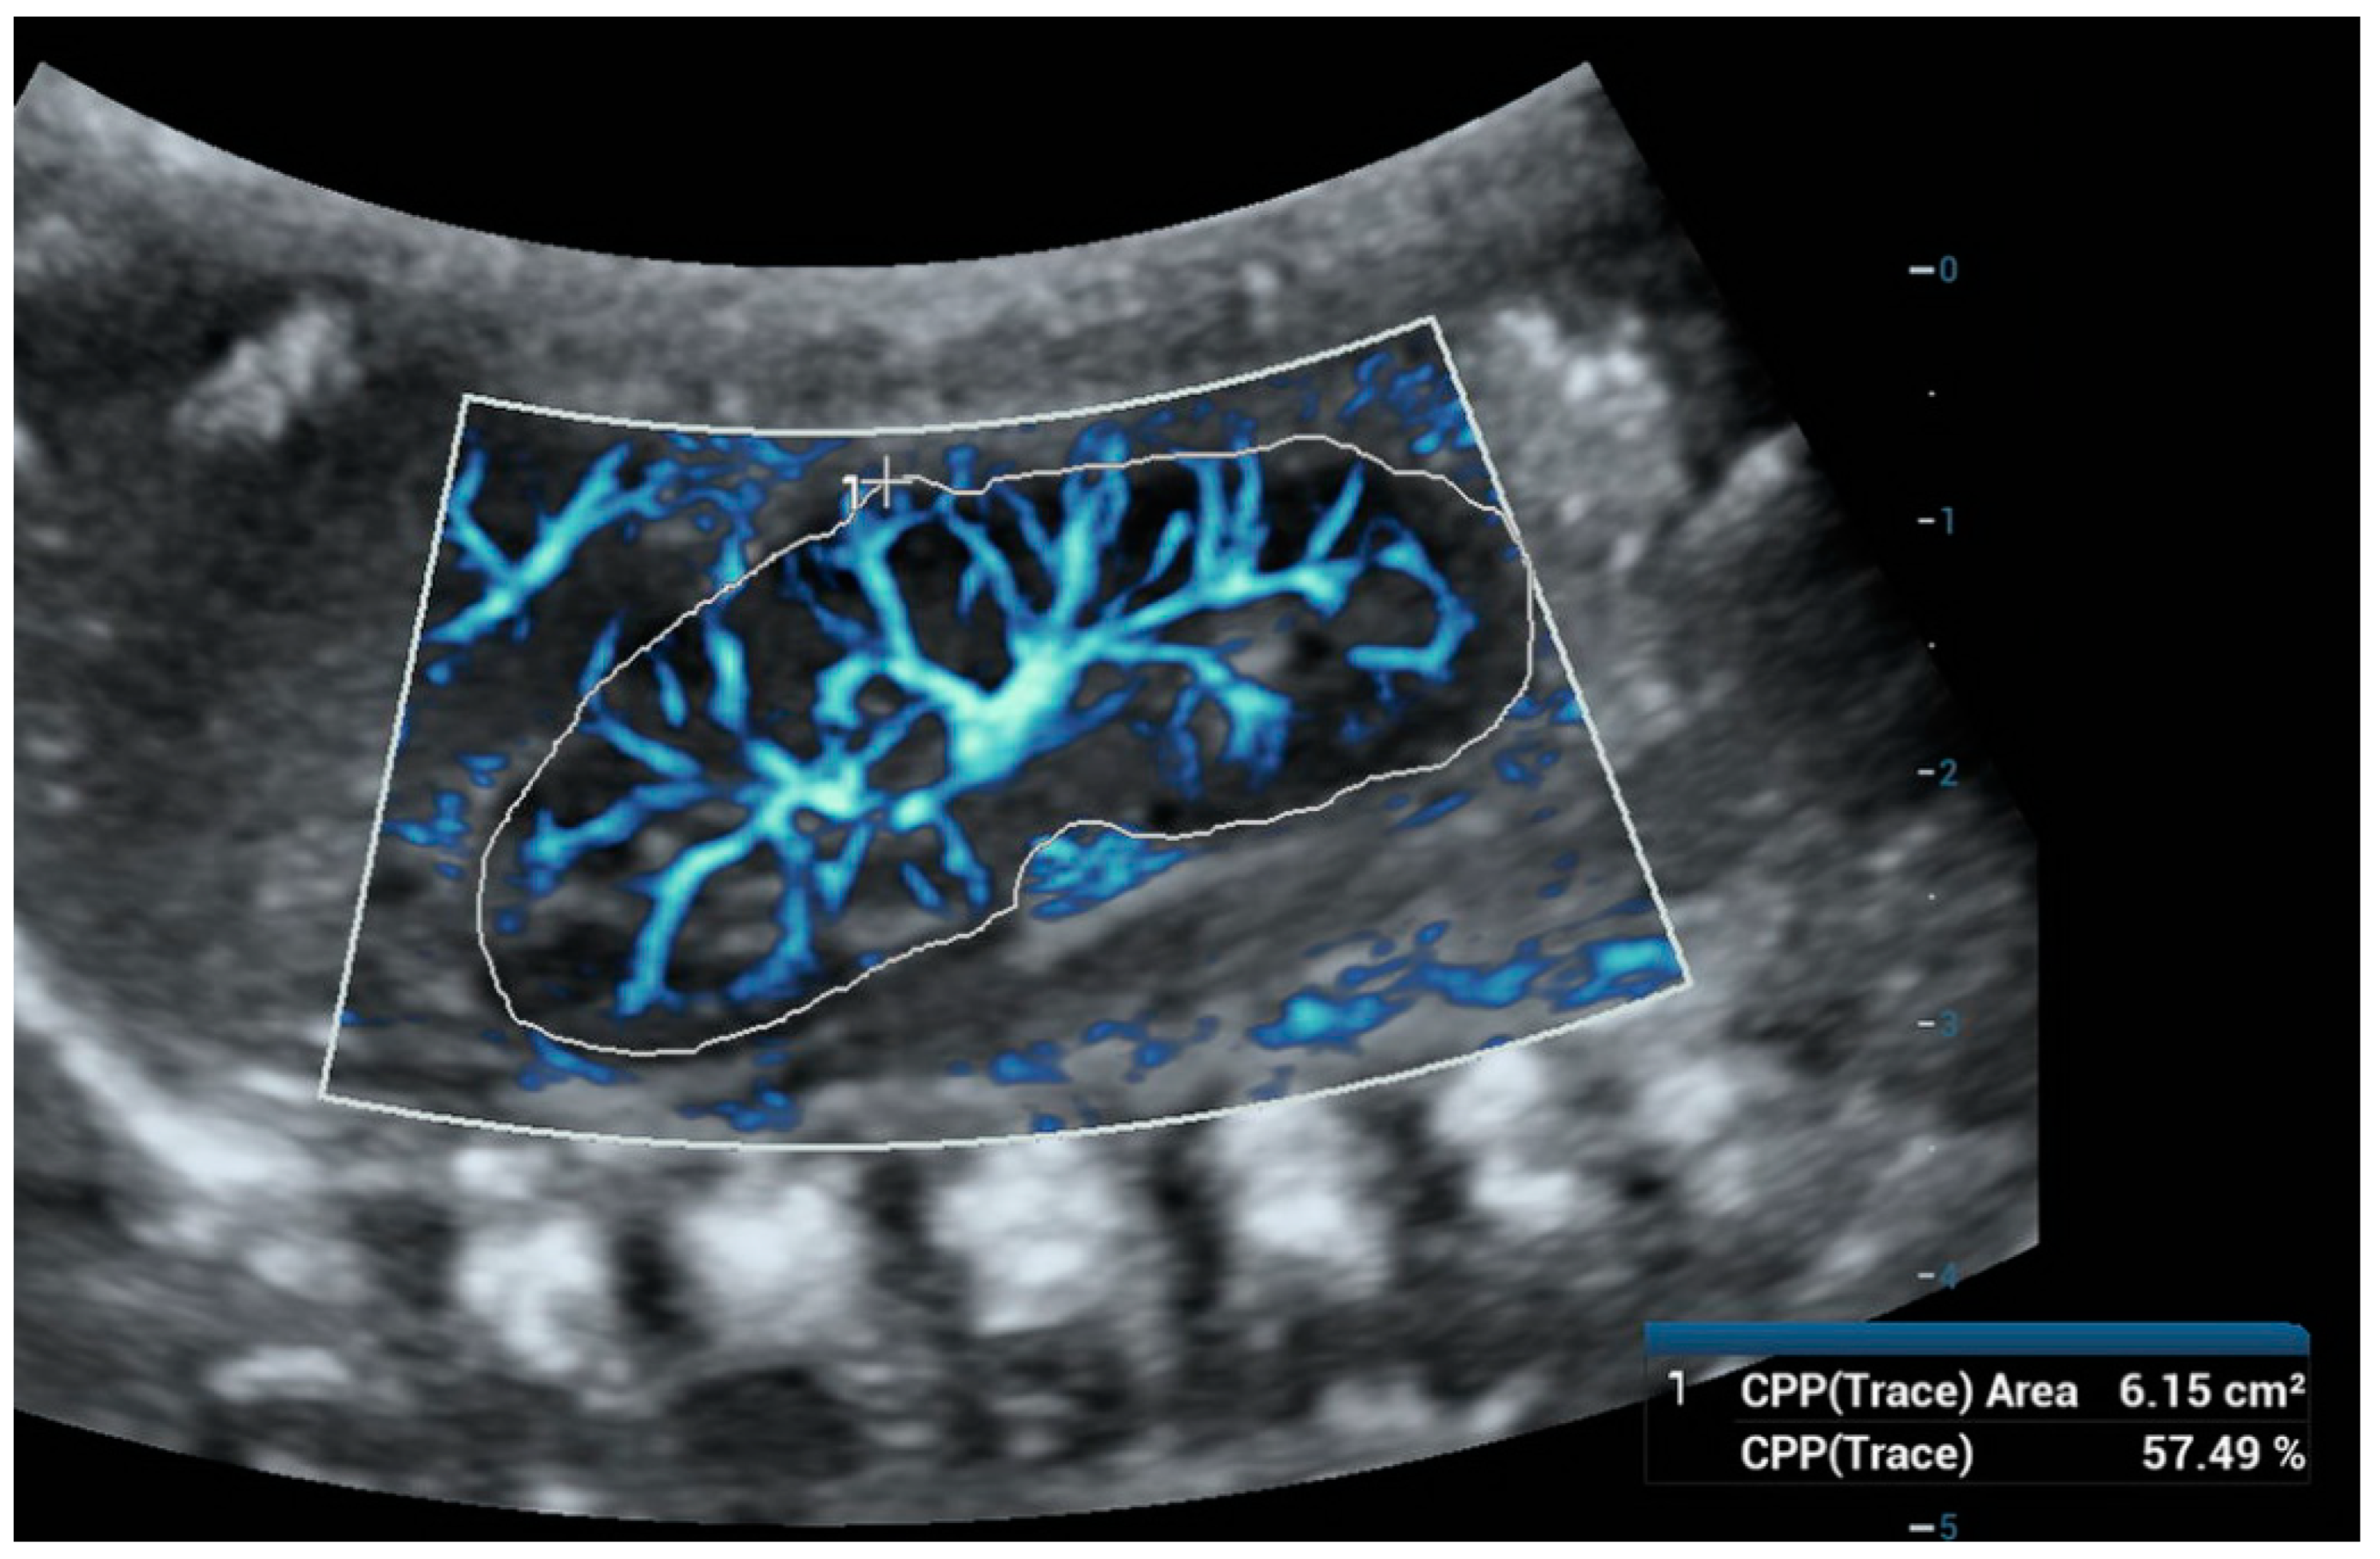

6. Ultra-Microangiography (UMA)